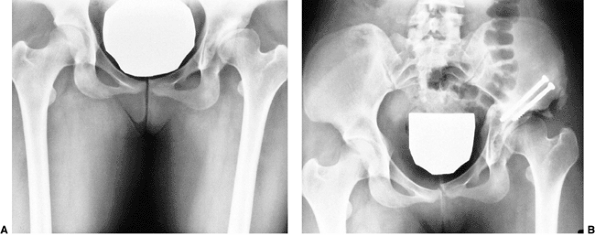

![]() |

Figure 24.26

The “gold standard” normal hip at maturity: note intact Shenton line, well-developed and appropriately shaped teardrop, down-sloping sourcil, and normal gothic arch above the sourcil. |